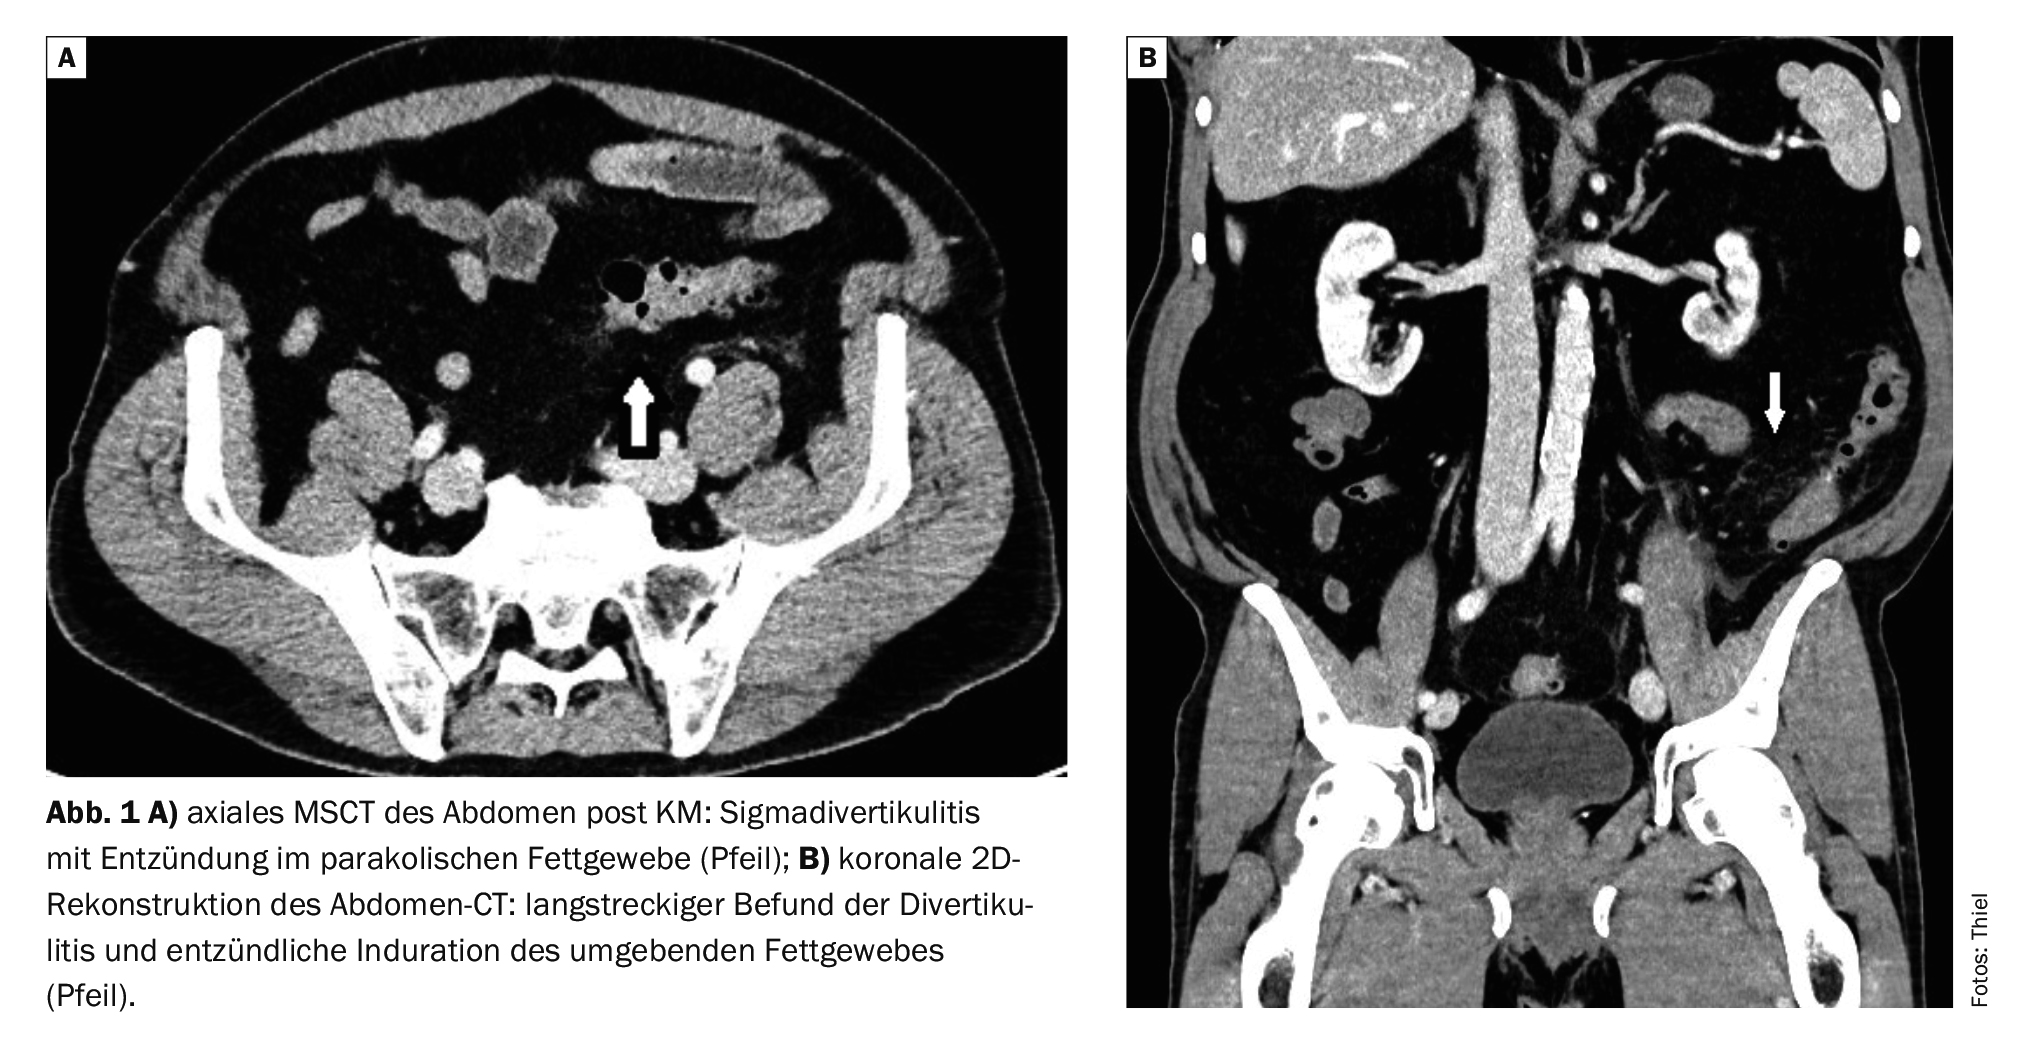

La tomodensitométrie met en évidence les diverticules dilatés et l’épaississement local de la paroi intestinale, excentrique ou circulaire [7]. Le tissu adipeux paracolique adjacent est épaissi de manière inflammatoire. Les inclusions gazeuses intramurales ou les produits de contraste peuvent être des indices d’une fistule initiale. Les lymphomes des tissus mous peuvent être détectés jusque dans la paroi abdominale ou thoracique. En cas de fistule entérovésicale, il y a de l’air dans la vessie. La coloscopie complète les informations fournies par la tomographie informatisée [2].

Dans l’étude de cas 1, un patient de 59 ans présentait des poussées récurrentes de diverticulite, principalement dans la région du côlon descendant et du sigmoïde (figures 1A et 1B). Le signe du stade inflammatoire aigu est une inflammation paracolique oedémateuse nette du tissu adipeux. Aucune indication de perforation ou d’abcès n’a été trouvée.